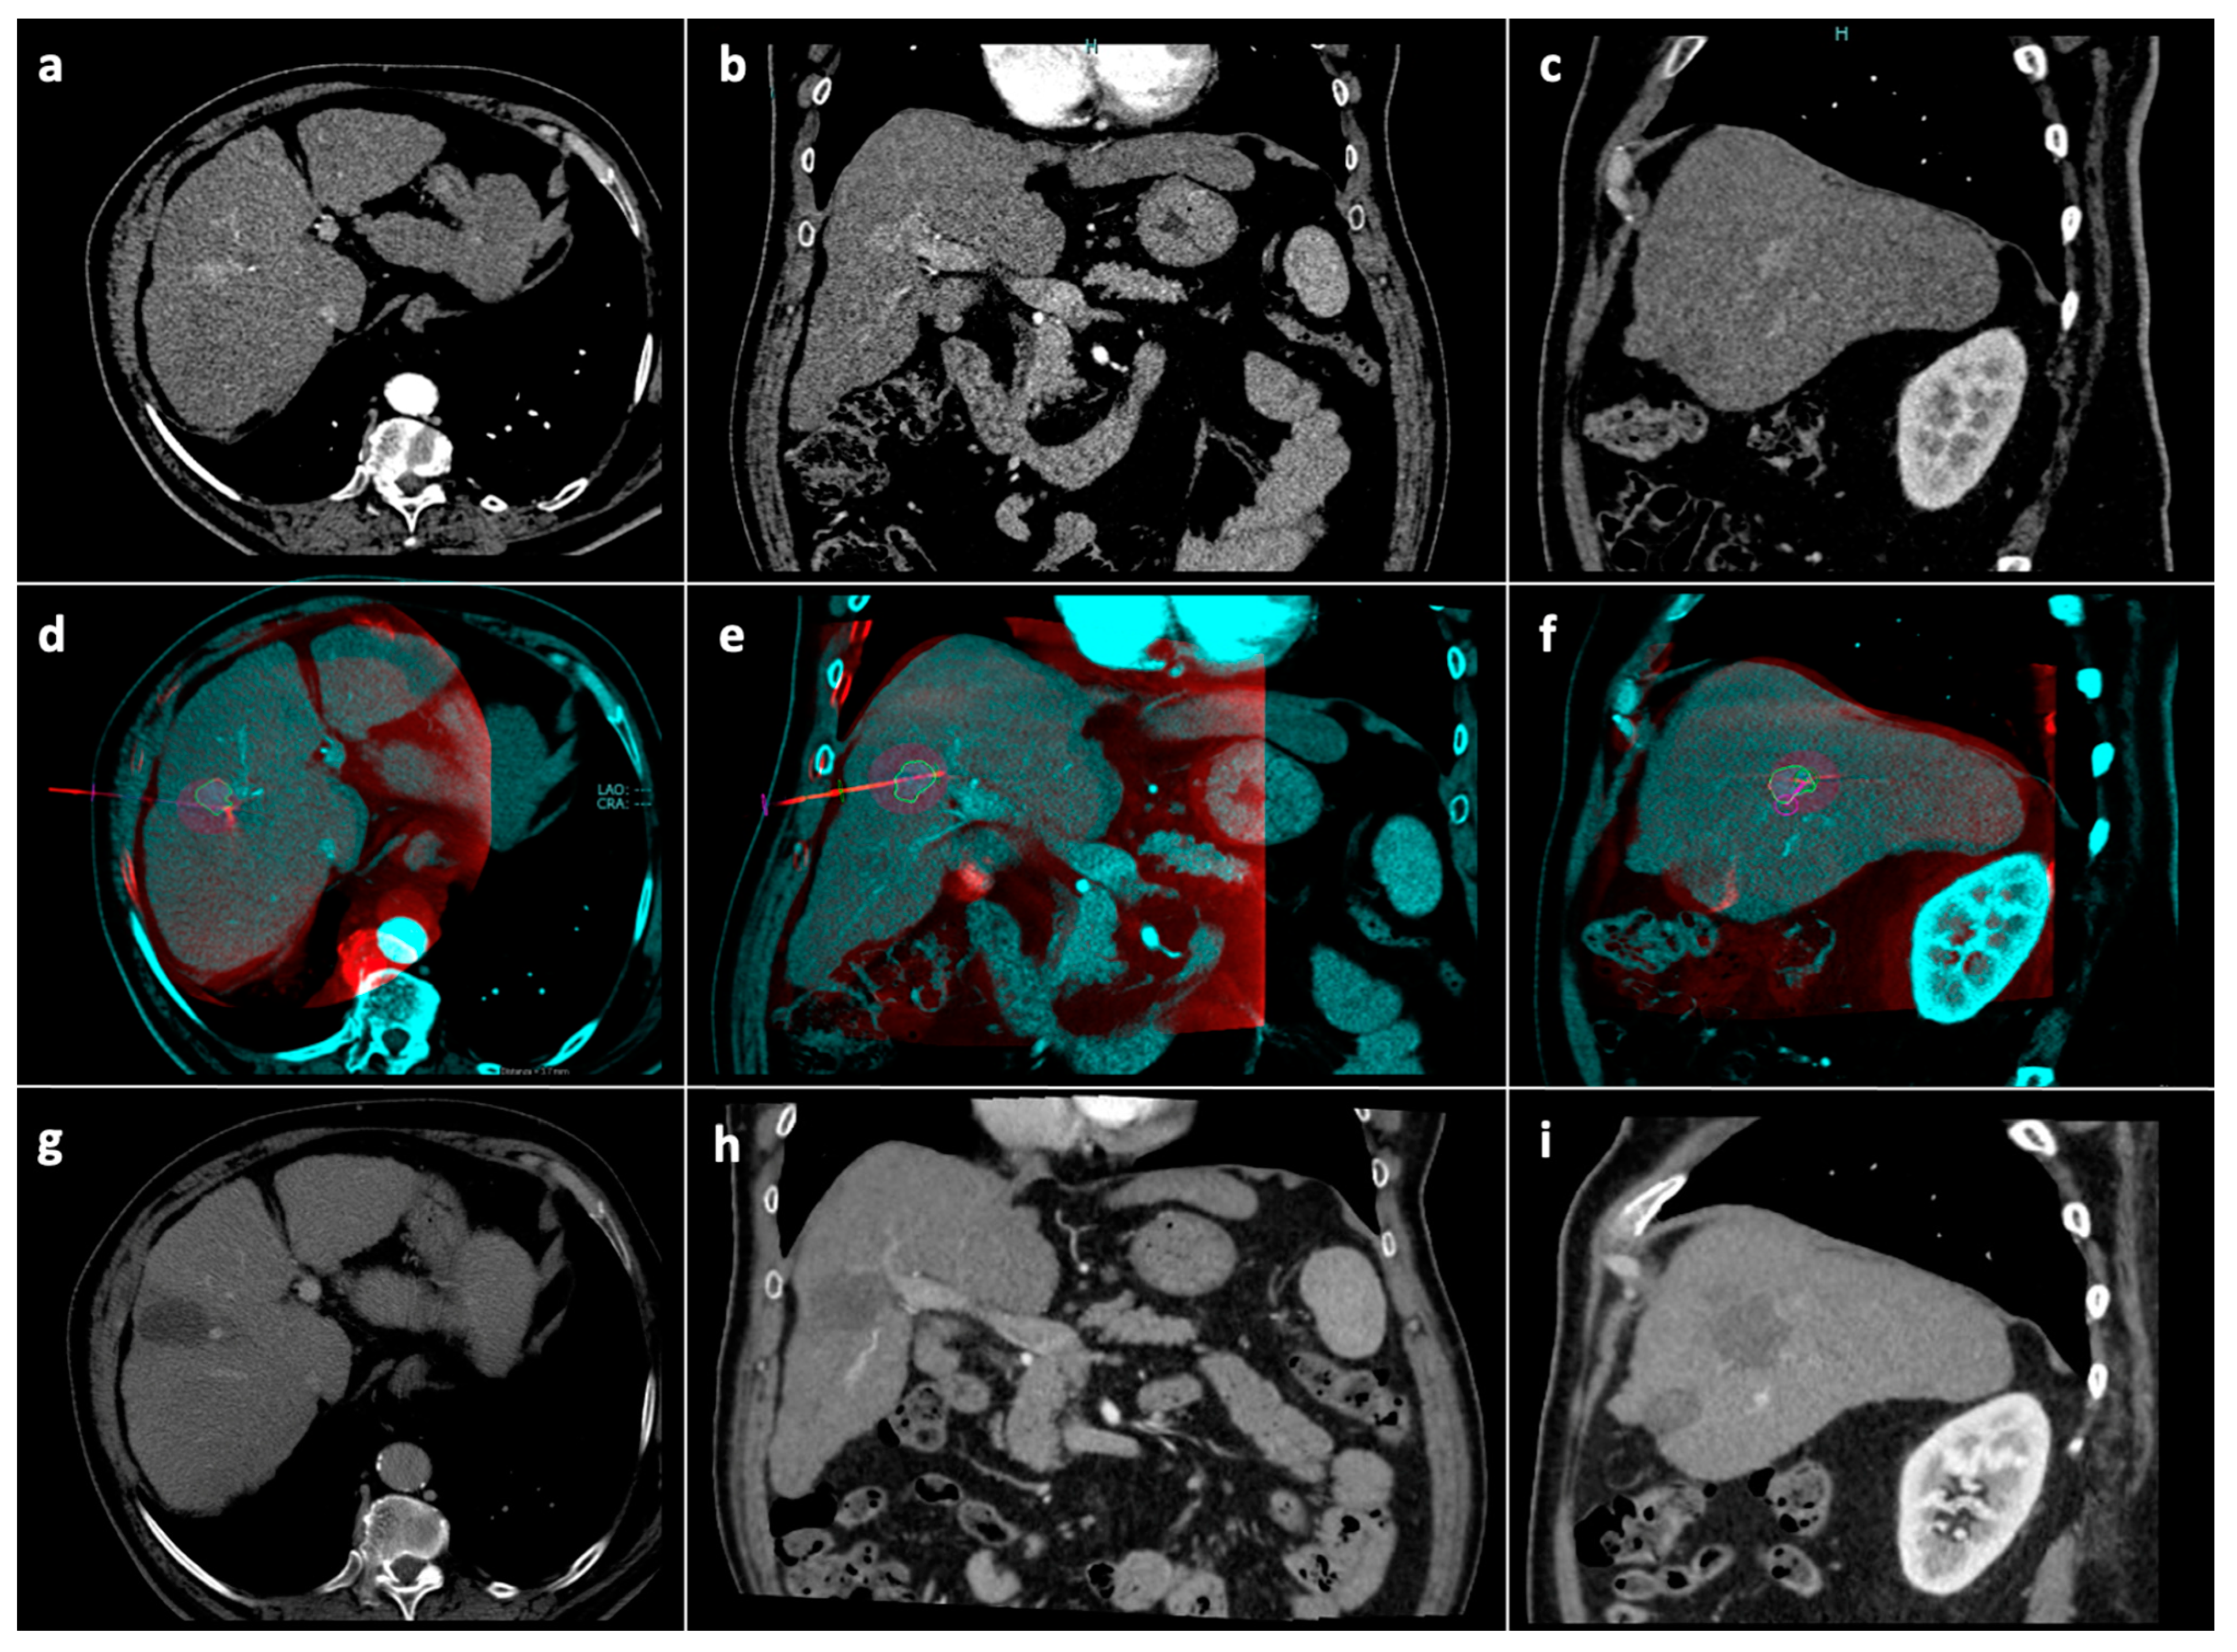

Radiological follow-up consisted of contrast enhanced CT/MRI 1 month after the procedure, then at 3 months and every 3–4 months thereafter (Figure 4). In the case of tumor detection during follow-up, the indication for a new treatment was discussed in a multidisciplinary setting. Patients undergoing new treatments were censored.

Figure 4. Tumor segmentation, ablation volume prediction and follow-up control. Pre-procedural CT arterial-phase images in the axial (a), coronal (b) and sagittal (c) planes. Intraprocedural fusion between preprocedural CT images showing the tumor (blue) and intraprocedural unenhanced CBCT images demonstrating the microwave antenna position (red) in the axial (d), coronal (e), and sagittal (f) planes; on the fused images, the volume (blue line) with a 5 mm safety margin (green line) is covered by the virtual predicted ablation volume (purple), which has been generated based on the antenna position and on the chosen ablation power and time. Follow-up CT images at 1-month in the axial (g), coronal (h) and sagittal (i) planes showing complete response. Abbreviations: CBCT: cone-beam computed tomography; CT computed tomography.